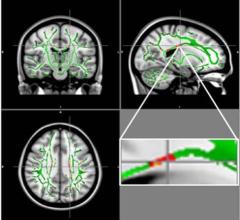

May 6, 2021 — Magnetic Resonance Imaging (MRI) images are usually meant to be static. But now, researchers from Mātai ...